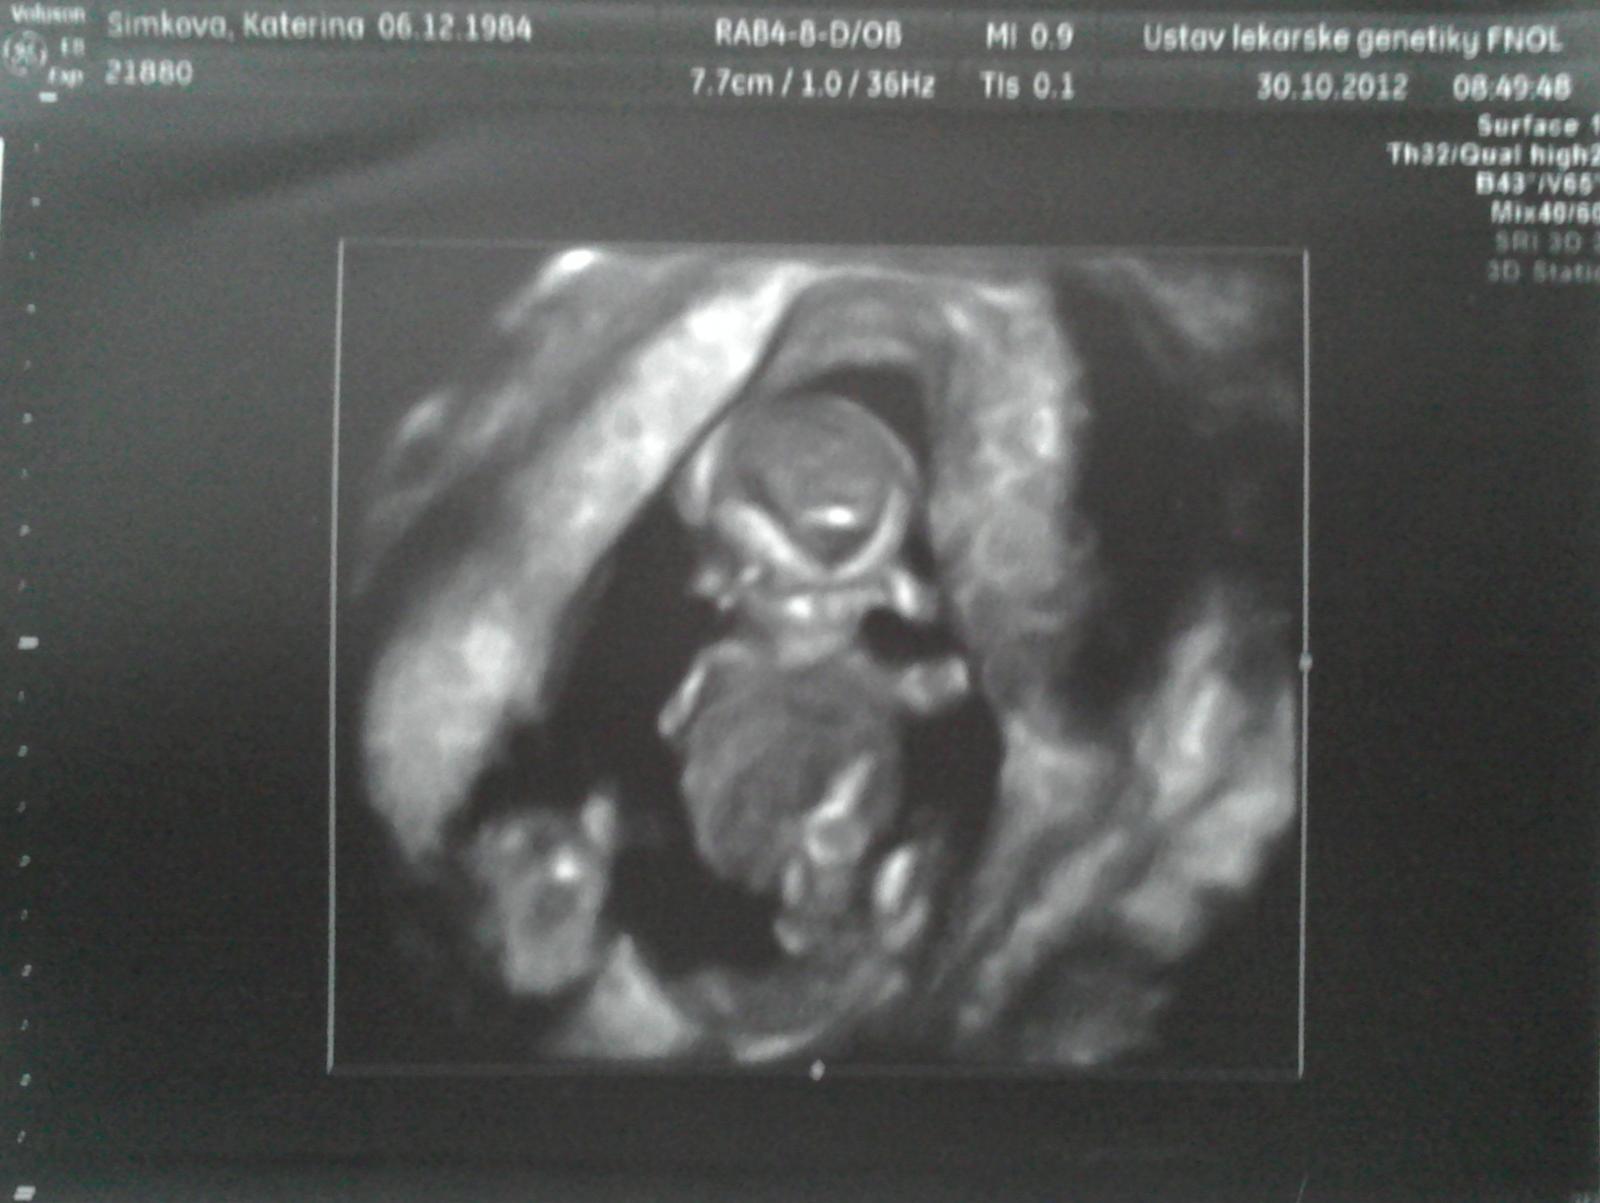

Ahoj holky, tak genetický screening je za námi. Horní miminko je krásné, zdravé, měří 5,25cm. 🙂 Dolní miminko je bohužel menší už o týden (minule o 3dny), nevyvíjí se dobře a nemá skoro žádnou plodovou vodu. ☹ Dle dr. nemůže přežít, s největší pravděpodobností se přestane vyvíjet a vstřebá se. Kontrola na genetice za 14dní. Kdyby to samo nevzdalo, tak by nás asi čekala redukce. Jsme v péči přímo prof. MUDr. Jiřího Šantavého, CSc., přednosta kliniky, tak aspoň tak. Jsme rádi, že jedno miminko je zdravé a pěkně se vyvíjí. Ale teď bude zase čekání, zda se to vyřeší samo nebo se tomu bude muset pomoct. ☹ Snad vše dobře dopadne a budeme mít alespoň jedno miminko 🙂 Napsala bych dřív, ale čekala jsem do půl čtvrté na telefonu kvůli celkovým výsledkům i s krví. 🙂